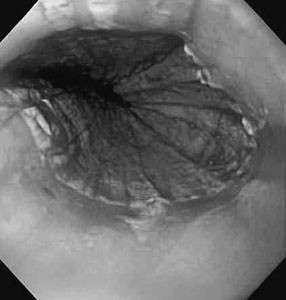

Fig. 1